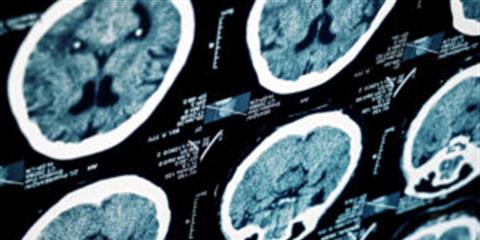

DALLAS, Texas. Traumatic brain injury can be difficult to treat. Some of the symptoms may not appear ...